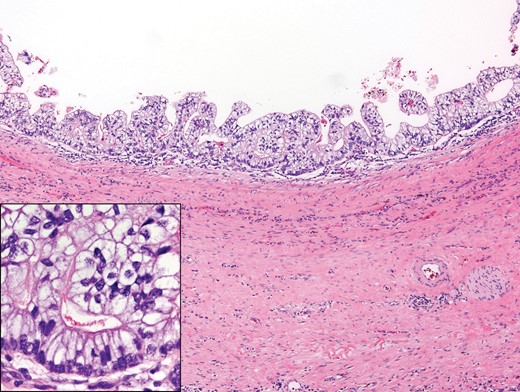

A 42-year-old patient with a history of clinical Stage I testicular non-seminomatous germ cell tumor (NSGCT) status post-left radical orchiectomy in 1986 (the exact pathology from his orchiectomy was not available) without additional treatment presented with right testis, back and flank pain. An abdominal computed tomography (CT) scan showed a retroperitoneal mass measuring 11.3 × 9.3 × 4.6 cm in the precaval area (Fig. 1) with negative tumor markers including β-HCG and alpha-fetoprotein. The patient underwent a testicular ultrasound of the right testis that showed microlithiasis but no hypodense mass. An exploratory laparoscopy with biopsy showed morphological features suggesting retroperitoneal idiopathic fibrosis. However, the clinical and imaging features as assessed by the urologist and oncologist were felt to be inconsistent with this possibility. The patient, therefore, underwent a CT-guided fine needle aspiration of the mass that showed extensively necrotic tumor.

An open laparotomy with resection of the mass and the retroperitoneal lymph nodes in a non-nerve sparing manner was performed. The pathological examination showed metastatic teratoma, with the lesion consisting of several cysts lined by stratified, mildly atypical glandular epithelial cells forming small papillae and encircled by smooth muscle (Fig. 2). Dense, fibrosclerotic and inflamed stroma was present peripheral to the mass. Immunohistochemical stains were positive for SALL4, supporting germ cell tumor origin and also positive for EMA, arguing against the possibility of yolk sac tumor.